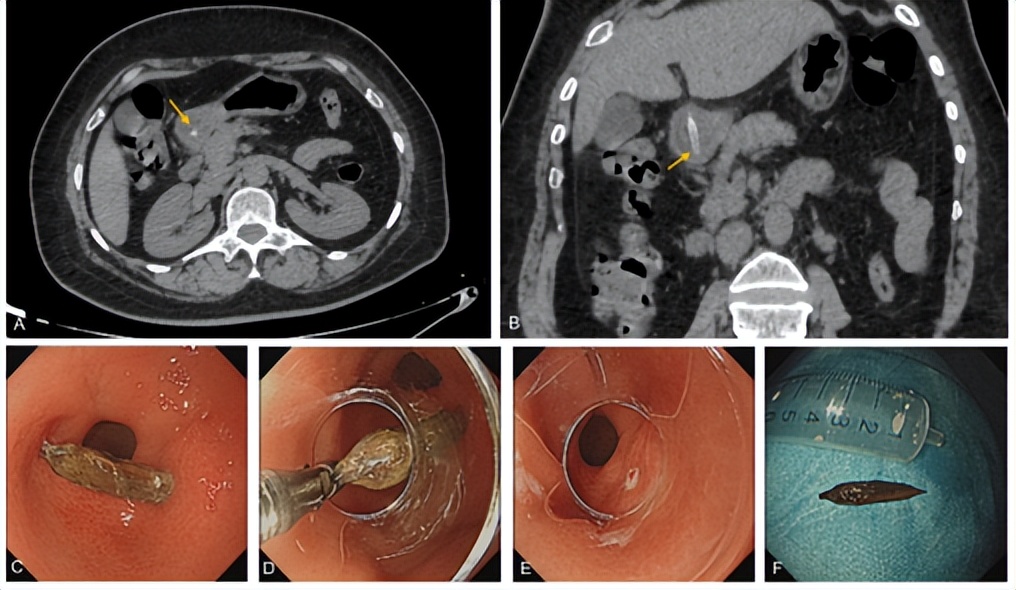

如果误吞枣核,并感到吞咽不适、胸骨后疼痛,应立即就医,急诊内镜常常可以取出卡在食管内的异物。但吞了枣核一段时间后,枣核可能已经到了肠道内,此时常规胃镜无法发现枣核;如出现肚子痛等不适,CT是能有效发现枣核的无创性检查。

同济医院放射科通过体外实验,证实CT可以发现所有种类的枣核。放射科医生通过对CT图像重建,可以清楚显示枣核的位置,以及判断是否发生穿孔、感染等并发症。

CT随访可以监测枣核在胃肠道内的移动情况及并发症的情况;复查CT未发现枣核时,则提示枣核已经排出体外。